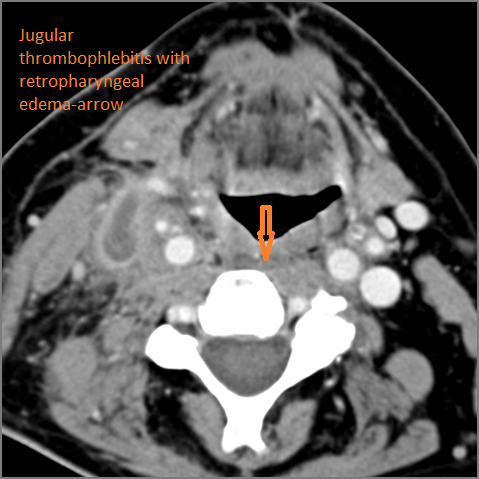

There is edema within the adjacent deep neck, retropharyngeal and/or prevertebral spaces. [Yes/No]

There is evidence of thrombus, thrombophlebitis or other occlusive or inflammatory process of the jugular vein. [Yes/No]